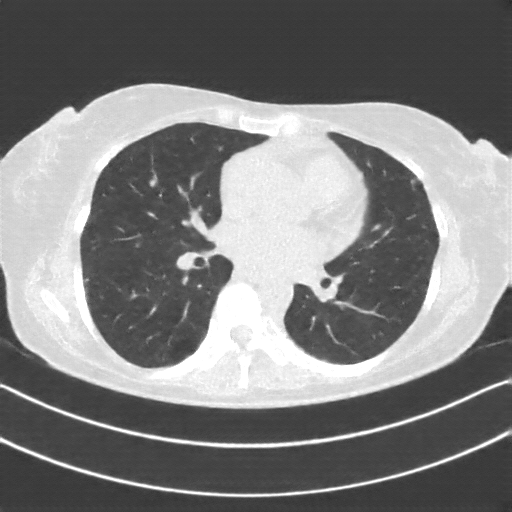

Image Grid

4×3 grid: Rows show different image types (Original NATIVE, Reconstructed NATIVE, Original VENOUS, Generated VENOUS), Columns show windowing techniques (No Window, Lung Window, Mediastinum Window)

Generated VENOUS CT scan (A→B translation)

No window - Raw intensity values

Generated VENOUS CT scan (A→B translation)

Lung window (WL -600, WW 1500 → Low −1350, High +150)

Generated VENOUS CT scan (A→B translation)

Mediastinum window (WL 40, WW 400 → Low −160, High +240)